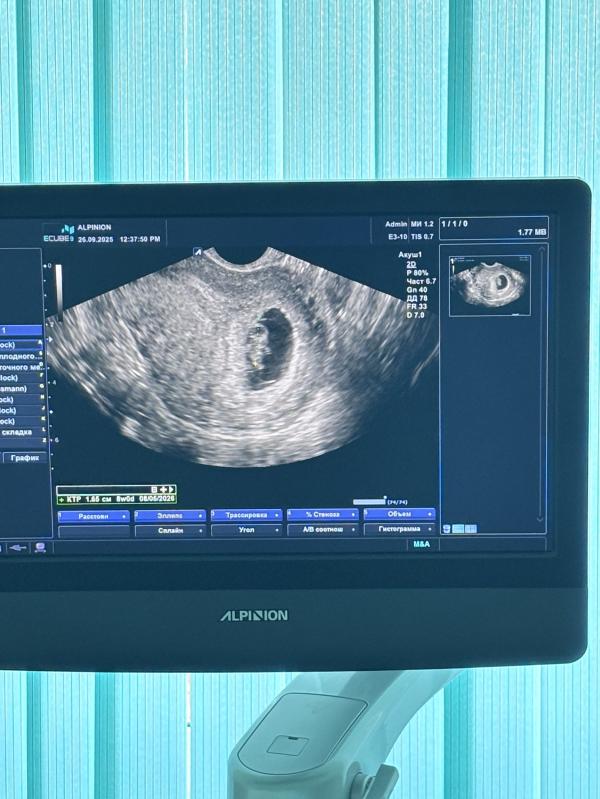

Человек растет,мать спокойна,тонус по задней стенке,магний принимать…На человечка уже похож,сердечко не стали включать,посмотрели его,все хорошо,сказал врач что тревожить не будем 🙏🏻🥰🙏🏻